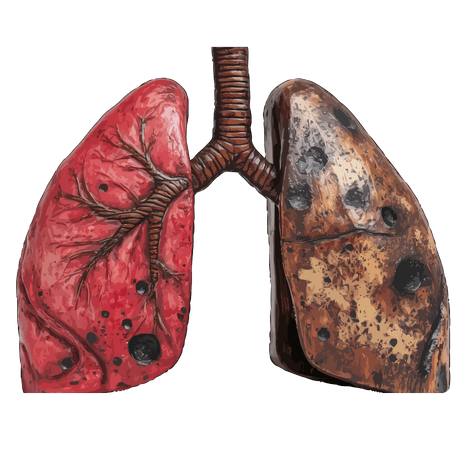

Tuberculosis (TB) is a serious infectious disease that mainly affects the lungs. It is caused by Mycobacterium tuberculosis bacteria and spreads through the air when an infected person coughs or sneezes. This condition can cause symptoms such as persistent cough, chest pain, coughing blood, fatigue, fever, night sweats, and weight loss. Without proper treatment, TB can damage lung tissues and may spread to other parts of the body.

Tuberculosis (TB) is a serious infectious disease in which the lungs (and sometimes other organs) become infected by Mycobacterium tuberculosis. It spreads through the air when an infected person coughs, sneezes, or talks. TB commonly causes symptoms such as persistent cough (sometimes with blood), chest pain, fever, night sweats, fatigue, and weight loss. If not treated properly, it can lead to severe lung damage and complications affecting overall health.

Tuberculosis (TB) is a treatable and curable condition when diagnosed early and managed properly. Along with standard anti-tubercular therapy (ATT), Ayurvedic treatment focuses on improving immunity (Ojas), reducing weakness, and supporting lung healing. It helps balance Vata and Kapha dosha, improve respiratory strength, and promote tissue repair through a holistic approach including herbal support, diet correction, and lifestyle management. This integrated approach aids recovery, prevents complications, and supports long-term respiratory health naturally.

Tuberculosis (TB) can develop gradually after infection with Mycobacterium tuberculosis, primarily affecting the lungs. It spreads through airborne droplets when an infected person coughs or sneezes. In many cases, symptoms appear slowly and may worsen over time if not treated. Early diagnosis and proper medical treatment are essential to prevent complications and ensure recovery. Along with standard treatment, supportive care helps strengthen immunity and improve overall health.

Imaging tests play an important role in confirming the extent and severity of Tuberculosis (TB) infection. These tests help doctors clearly visualize the lungs and identify abnormalities such as infection, cavities, fluid buildup, or tissue damage caused by Mycobacterium tuberculosis.

These imaging techniques are essential for accurate diagnosis, assessing disease progression, and planning appropriate treatment. Early imaging helps in detecting TB at an early stage, preventing complications, and improving recovery outcomes.